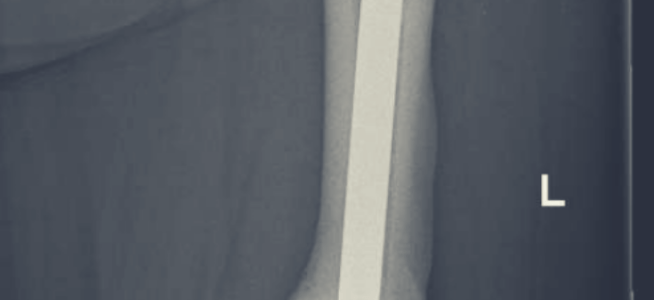

Bigger isn't always better in life. I'm not talking about weight size or the size of your bank balance or home, I'm talking about bigger bones. If you research bone disease on "Dr Google" you'll find copious amounts of information about Osteoporosis, low bone density and the importance of having good healthy bones. Try researching high … Continue reading Bigger Isn’t Always Better In Life

The Spinal Surgery Recovery Road

I'm a week post L4/L5 laminectomy and decompression surgery. I've been home from hospital for 5 days and the road to recovery has begun. Well sort of. I really feel like I'm still in survival mode. My Surgeon tells me we did the right thing proceeding with this surgery. My spinal cord was severely compressed … Continue reading The Spinal Surgery Recovery Road